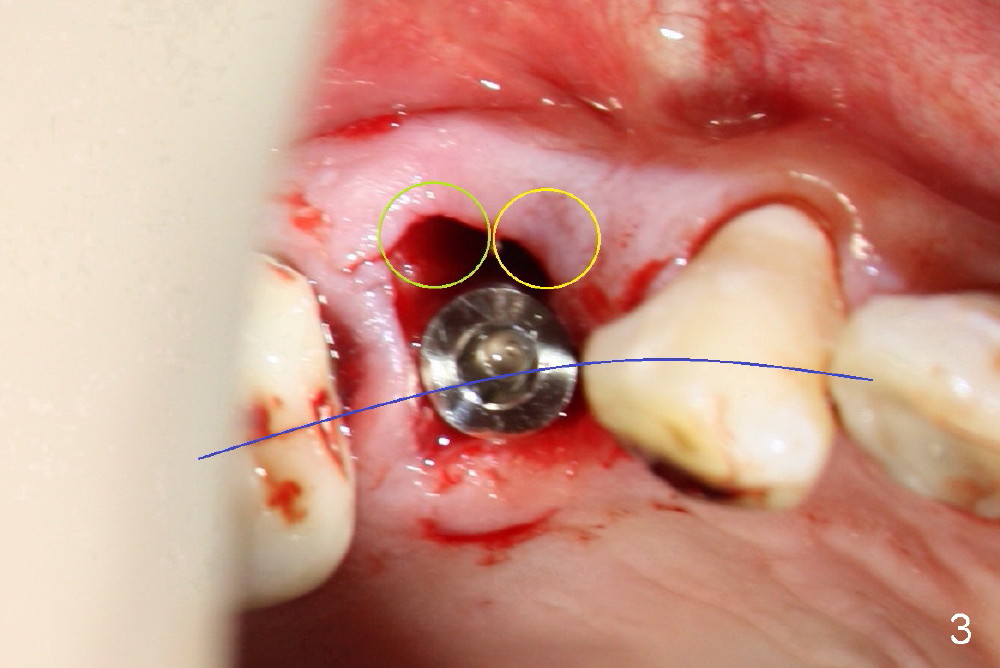

When the tooth is extracted, the two sockets (Fig.2 yellow circles, where the irrigation syringe is) are found to be buccally located, creating cantilever effect and probably leading to restoration failure/root fracture. There is bone palatal to the sockets (*). Bicon reamers are used to form osteotomy and collect autogenous bone at the same time (because of 50 RPM). A 5x17mm implant is placed, in alignment with arch form (Fig.3 blue curved line). The future restoration will be along the long axis of occlusion. Therefore the immediate implant achieves "instant orthodontic result".